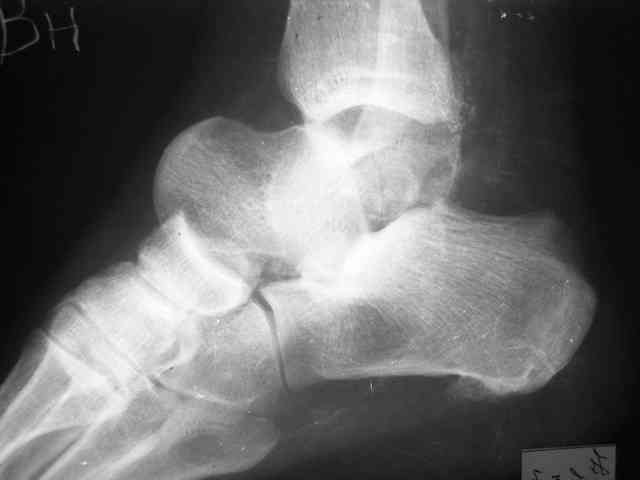

Re: Редкое повреждение - полный вывих тарана!

Уважаемый Александр! Как обещал представляю Р-граммы и операционные фото.

Ваши (лично ваши) рекомендации - астрагалэктомия-аппаратный пяточно-большеберцовый артродез с одновременным удлинением голени - правильно?